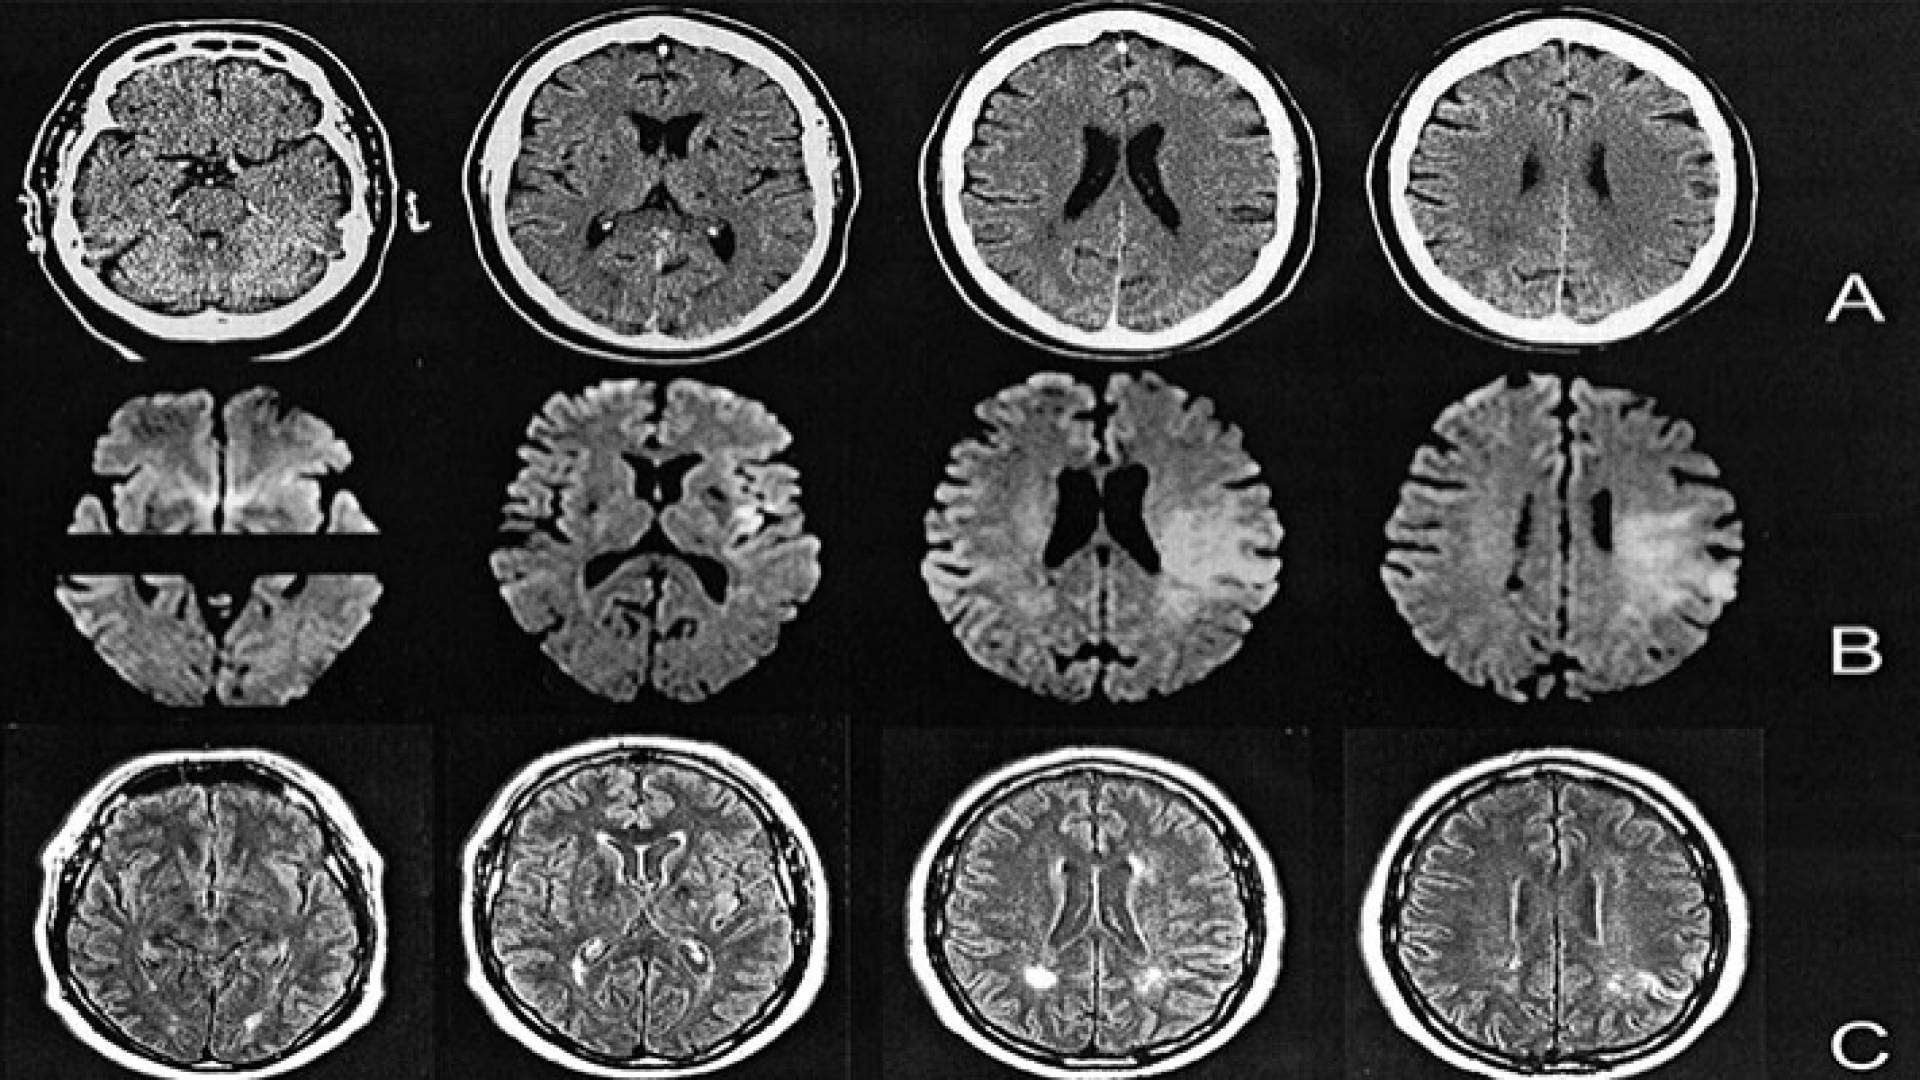

صورة طبقية للدماغ